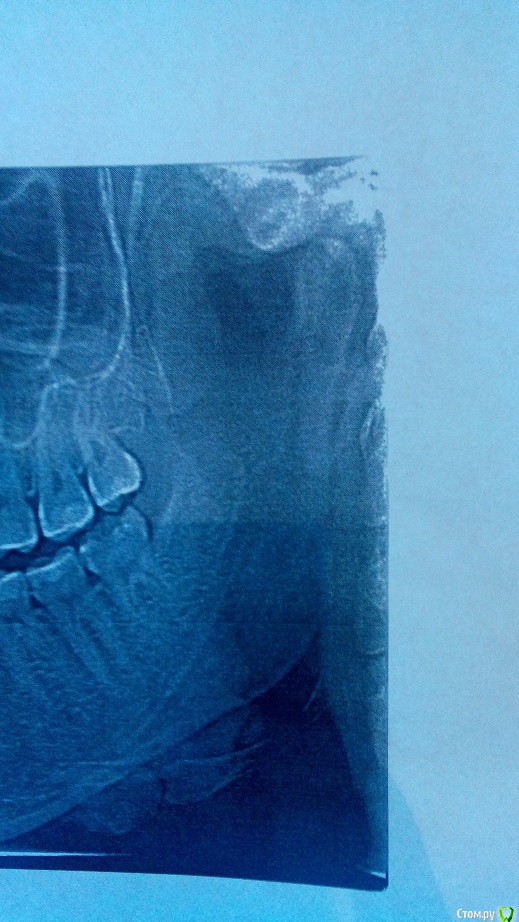

Ситуация следующая,в сентябре сделала снимки и ортодонт сказал,что головка сустава смещена

сегодня 12 декабря сделала опг снова,к сожалению сустав там плохо,как мне кажется

хотелось бы услышать ваши мнения,уважаемые врачи

возможно ли довести до нормального состояния прикус,зубы без операции??

так же интересует удаление восьмых зубов в моем случае ,так как один хирург сказал,что отказывается удалять мне правую восьмерку ( а с суставом проблема к слову справа) ,так как повредит мне